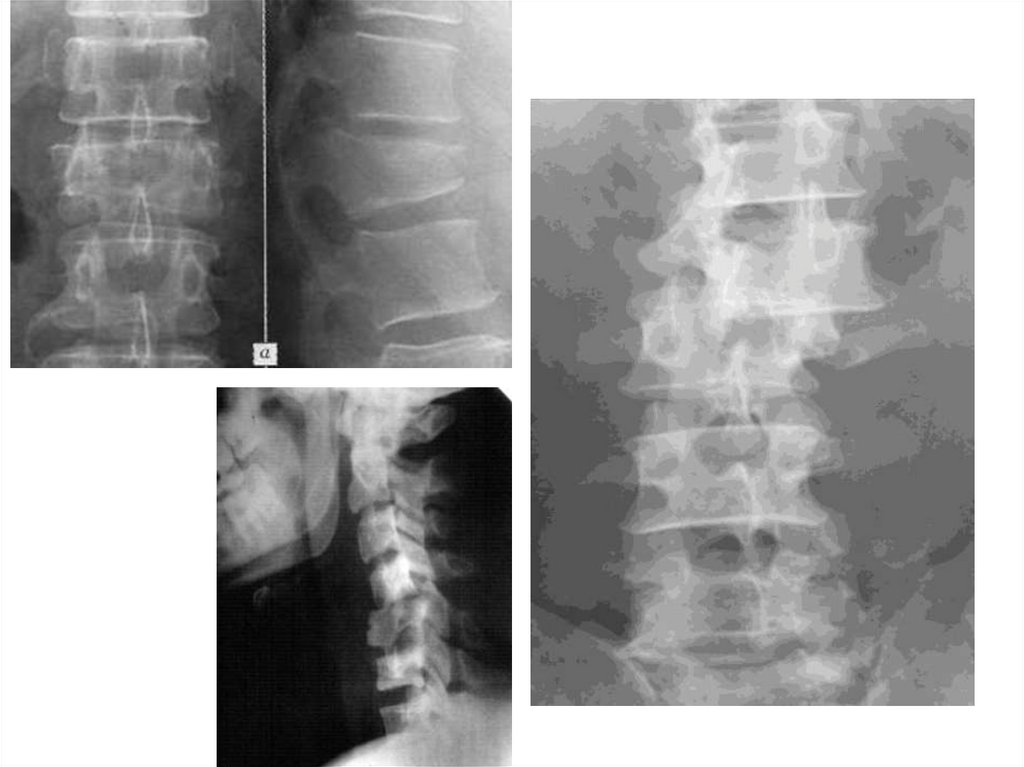

Переломы позвонков

• Переломы тел позвонков

• Переломы дуг

• Переломы отростков

Типы повреждения позвоночника:

• Компрессионный (А)

• Дистракционный (В)

• Ротационный (С)